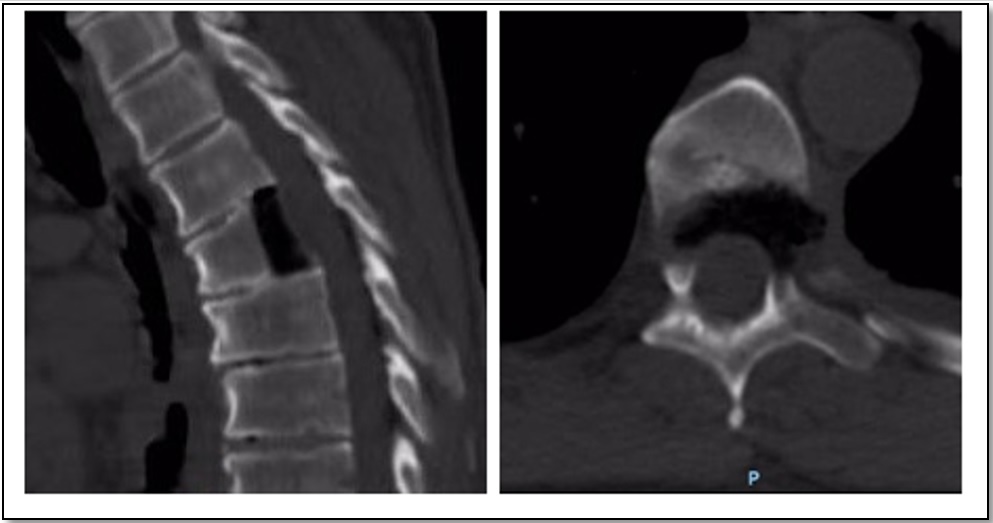

Existen múltiples técnicas para la descompresión medular en la columna torácica, cada una con sus ventajas y desventajas y con distintos requerimientos de destrezas quirúrgicas. Se han desarrollado técnicas mínimamente invasivas que disminuyen las tasas de morbilidad, con buenos resultados funcionales. Se presenta el caso de un hombre de 64 años, con clínica de compresión medular, una hernia de disco central, calcificada a nivel del quinto disco torácico, migrada hasta el borde inferior de la sexta vértebra torácica, con franca compresión medular. Se realizó un abordaje lateral transpleural mínimamente invasivo, con una corpectomía parcial posterior de la sexta vértebra, sin fijación adicional. El paciente tuvo una buena evolución, sin progresión del cuadro neurológico ni dolor costal residual. Los abordajes laterales mínimamente invasivos son técnicas válidas para tratar patologías compresivas de la columna torácica, con bajas tasas de morbimortalidad y una rápida recuperación. Abstract There are multiple techniques for spinal cord decompression in the thoracic spine, each with its advantages and disadvantages, and requiring different surgical skills. Recently, minimally invasive techniques have been developed, reducing morbidity rates and achieving good functional results. We present the case of a 64-year-old male with spinal compression symptoms, central disc herniation calcified at the fifth thoracic vertebra, which migrated to the lower end of the sixth thoracic vertebra. Diagnosis was clear for spinal cord compression. Partial posterior corpectomy of the sixth vertebra was performed with a minimally invasive transthoracic transpleural lateral approach and without additional fixation. The patient had a good outcome on follow-up, without progression of neurological symptoms or residual rib pain. Minimally invasive lateral approaches are valid techniques for the treatment of compression disorders of the thoracic spine, with low rates of morbidity and mortality, and a rapid recovery.Descargas